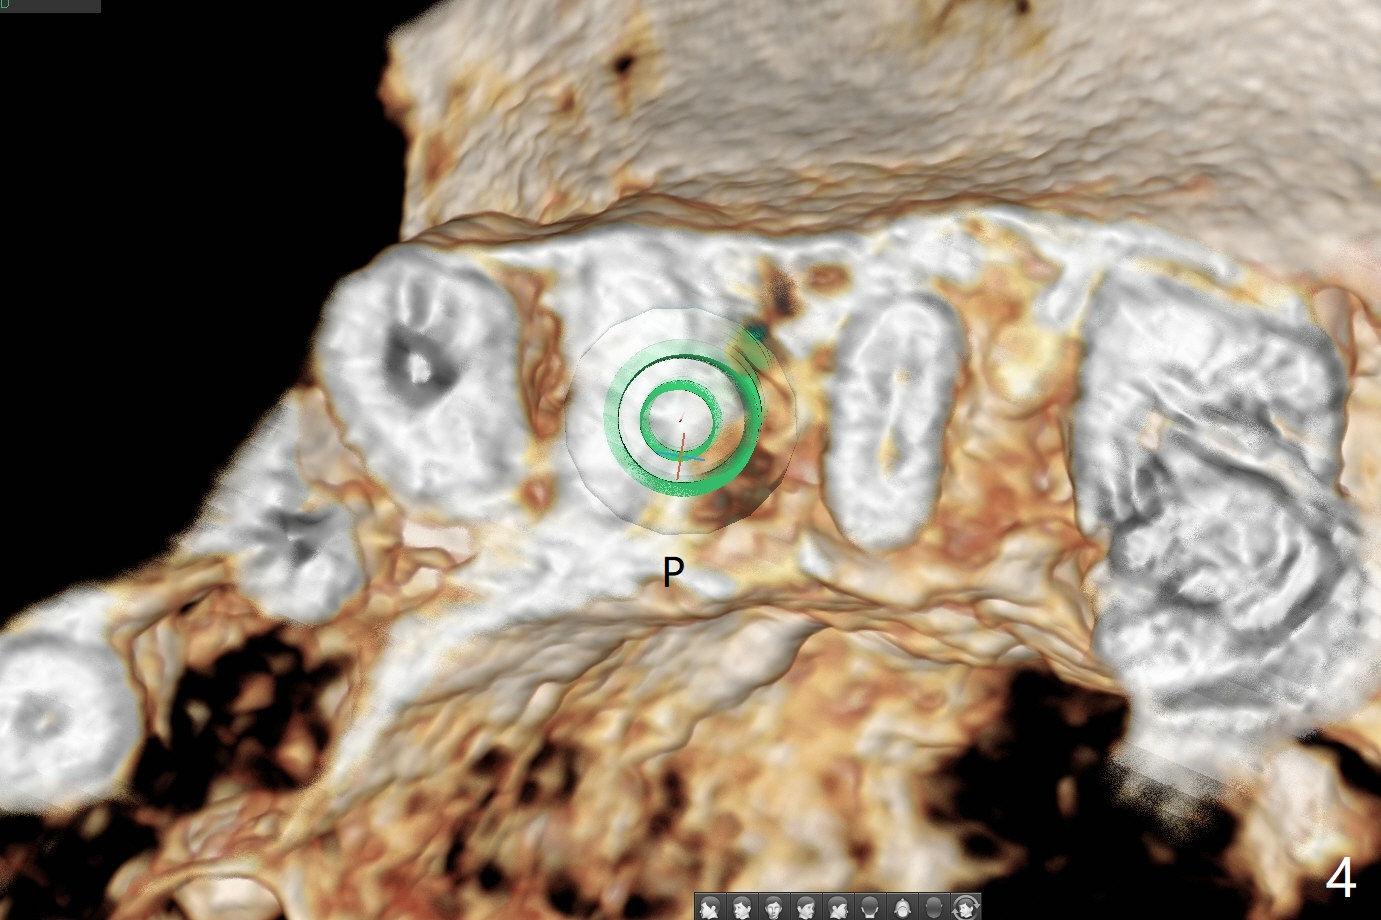

68岁女右上4个植牙后(图一),左上4(12号牙)根尖周围炎,根管闭锁(图二),牙周袋9毫米。切割3,4连冠,拔除4,为了减少腭侧骨板吸收,植体也不要植入太腭侧(图三,四)。其实顺腭侧根钻洞偏近中,很难纠正,最后位点保存